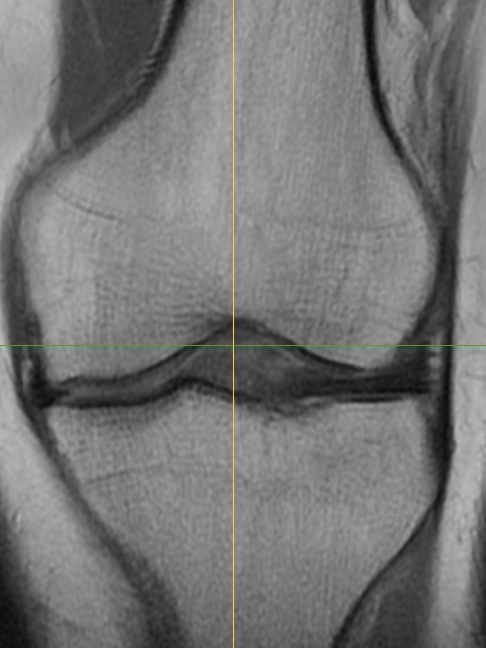

I tore the meniscus in my left knee last year. Most 3D knee models online are right knees, so I decided to make my own left-knee model from my scan. The MRI I used was from a later skiing accident, months after the original meniscus tear had healed, so the dataset reflects the reinjury work-up, not the initial tear.

Caption: MRI of the left knee from the skiing accident.